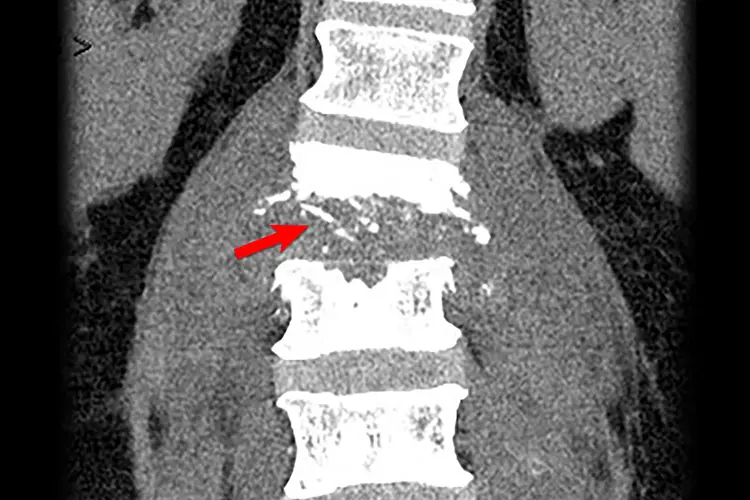

- CT scans to see your spine in more detail compared to X-rays

Your doctor will then look at the results to figure out how far the infection has spread and if any abscesses (pocket of pus) have formed. Doctors typically prescribe antibiotics or antifungals to treat osteomyelitis, depending on the cause of the infection. If you have an abscess, your doctor may use a needle to drain it. If the infection is very bad or if you have a high risk of complications, you may need surgery.

Discitis is when the discs in between your vertebrae, known as intervertebral discs, are inflamed. Some believe that discitis and osteomyelitis are stages of the same disease.